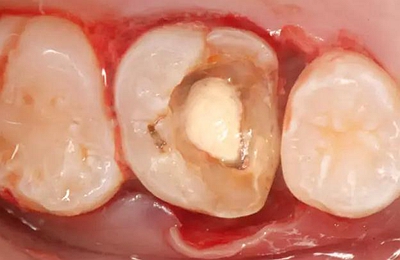

患者男性,35歲,B6銀汞充填后食物嵌塞,要求重新充填,口內(nèi)檢查見B6近中鄰頜面銀汞充填物,局部缺損,有繼發(fā)齲,去除原充填物及繼發(fā)齲,發(fā)現(xiàn)齲壞位于牙齦下方,給予冠延長(zhǎng)手術(shù),同期嵌體預(yù)備,后一次性取模。(同樣設(shè)計(jì)為齦上邊緣)

硅橡膠取模后,灌注模型,科爾琥珀樹脂制作嵌體。

一周后拆線,口內(nèi)試戴合適,粘結(jié)嵌體。